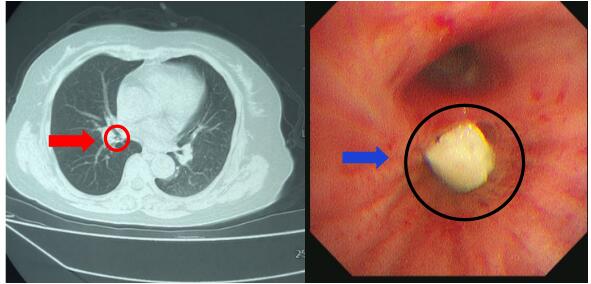

患者,女性,57岁,体检发现肺占位;

5CDF

为了进一步明确,我们进行支气管镜检查,使用超细支气管镜进入左肺下叶外基底段,并于外基底段给予超声探查活检后,病理诊断“肺腺癌”。